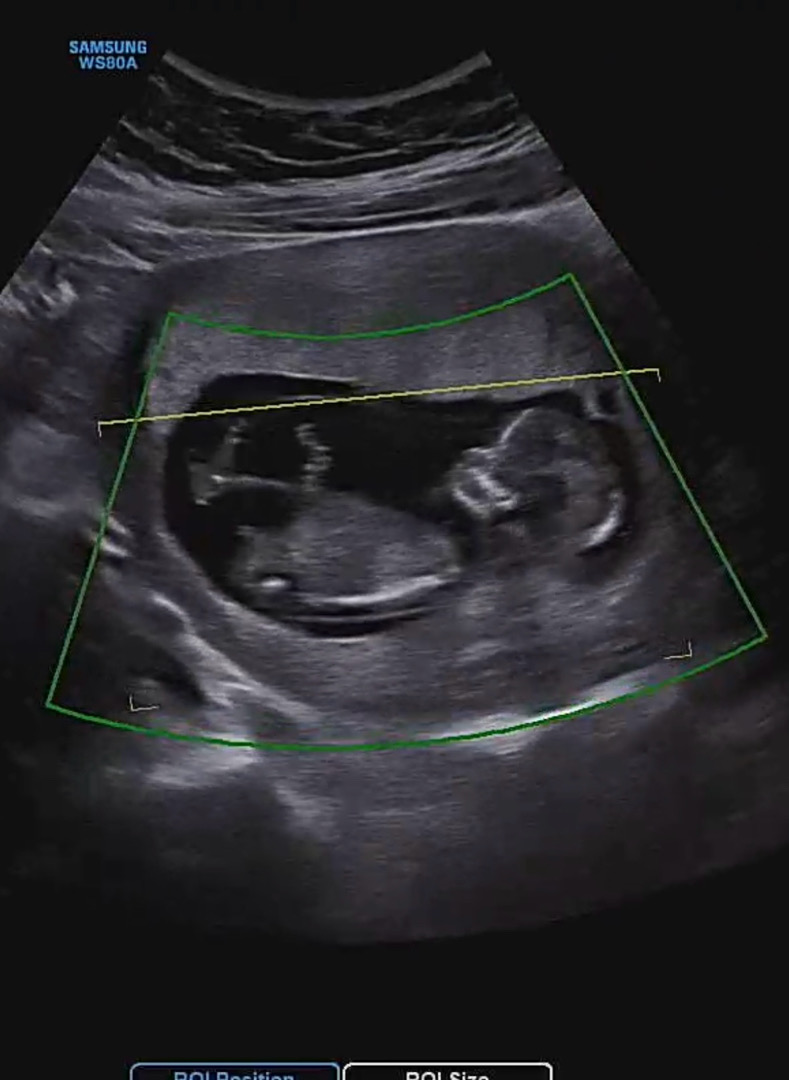

12주1일 각도법한번 봐주세요!

봐도봐도 애매해서😂😂 다들 한번씩 봐주시면 감사하겠습니당